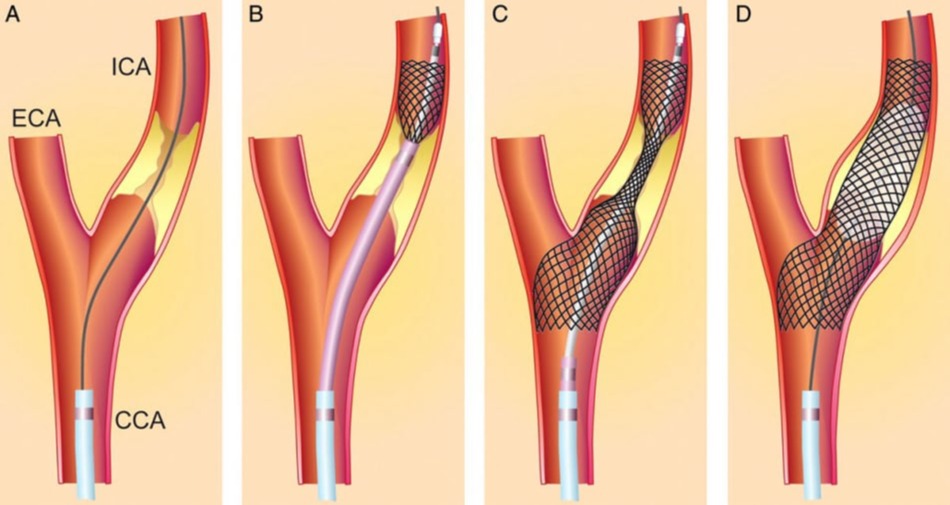

Η αγγεοπλαστική και η τοποθέτηση στεντ στην καρωτίδα (carotid stenting) είναι επεμβάσεις που χρησιμοποιούνται για την αντιμετώπιση στενώσεων στις καρωτίδες αρτηρίες. Αυτές οι αρτηρίες, που βρίσκονται στον λαιμό, μεταφέρουν αίμα προς τον εγκέφαλο. Οι στενώσεις αυτές μπορεί να οφείλονται συνήθως σε αθηροσκλήρωση, η οποία είναι η απόθεση αθηρωματικών πλακών στις αρτηρίες.

Η αγγεοπλαστική και η τοποθέτηση στεντ στην καρωτίδα (carotid stenting) είναι επεμβάσεις που χρησιμοποιούνται για την αντιμετώπιση στενώσεων στις καρωτίδες αρτηρίες. Αυτές οι αρτηρίες, που βρίσκονται στον λαιμό, μεταφέρουν αίμα προς τον εγκέφαλο. Οι στενώσεις αυτές μπορεί να οφείλονται συνήθως σε αθηροσκλήρωση, η οποία είναι η απόθεση αθηρωματικών πλακών στις αρτηρίες.